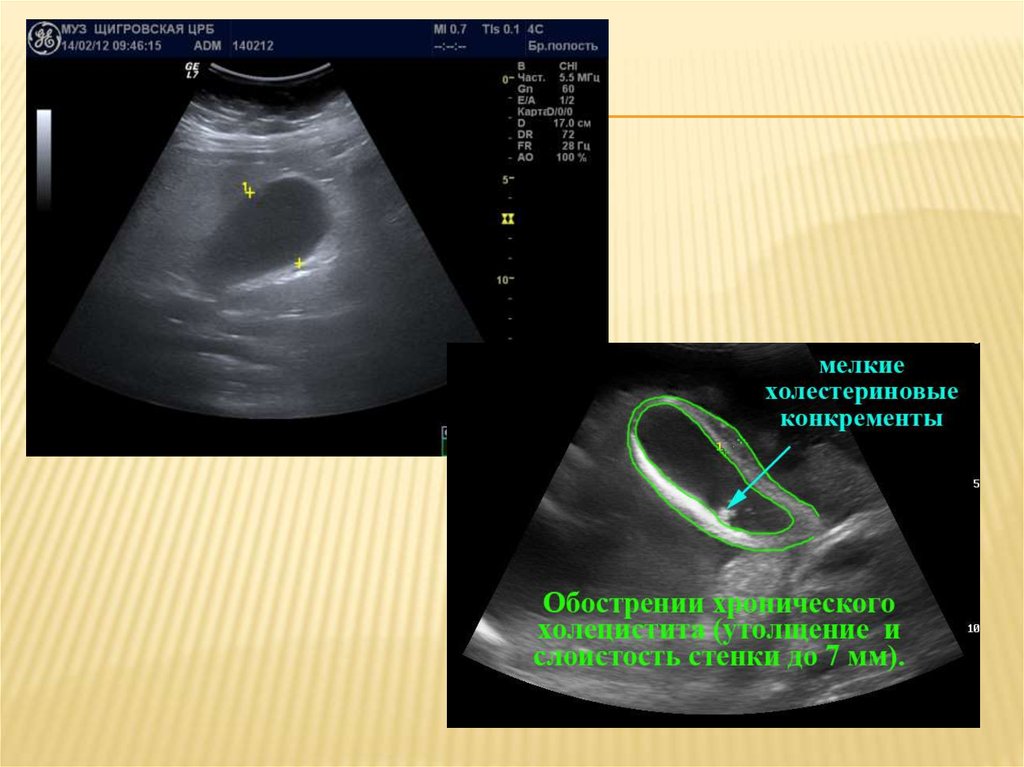

Диагностируют холецистит при

беременности, также как и в обычных

случаях. При этом:

Производится осмотр врачом

(выслушивание жалоб, пальпация живота).

Сдаются анализы крови, мочи, кала.

Проводится УЗИ органов желудочнокишечного тракта.

Для диагностики острого холецистита при

беременности используют УЗИ. Признак

обструкции — расширение желчных протоков.

Если при УЗИ патологии не выявлено, а

симптомы острого холецистита выражены,

проводят холесцинтиграфию с производными

иминодиуксусной кислоты (например, HIDA —

2,6-диметилиминодиуксусной кислотой).

Рентгенографию для диагностики острого

холецистита при беременности с

использованием контрастных веществ проводят

только при экранировании живота.